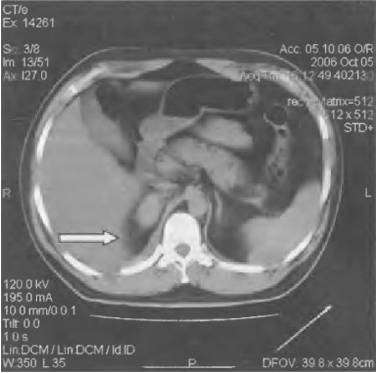

Гидронефроз

Прогрессирующее расширение собирательных полостей почек приводит к их дисфункции.

Характер и локализация боли

Гидронефроз вызывает ноющие боли в области живота, боков, поясницы и крестца.

При поражении правой почки болезненность ощущается преимущественно справа.

Диагностика и лечение

Диагноз ставят на основе анализа крови, УЗИ почек, экскреторной урографии, КТ и МРТ.